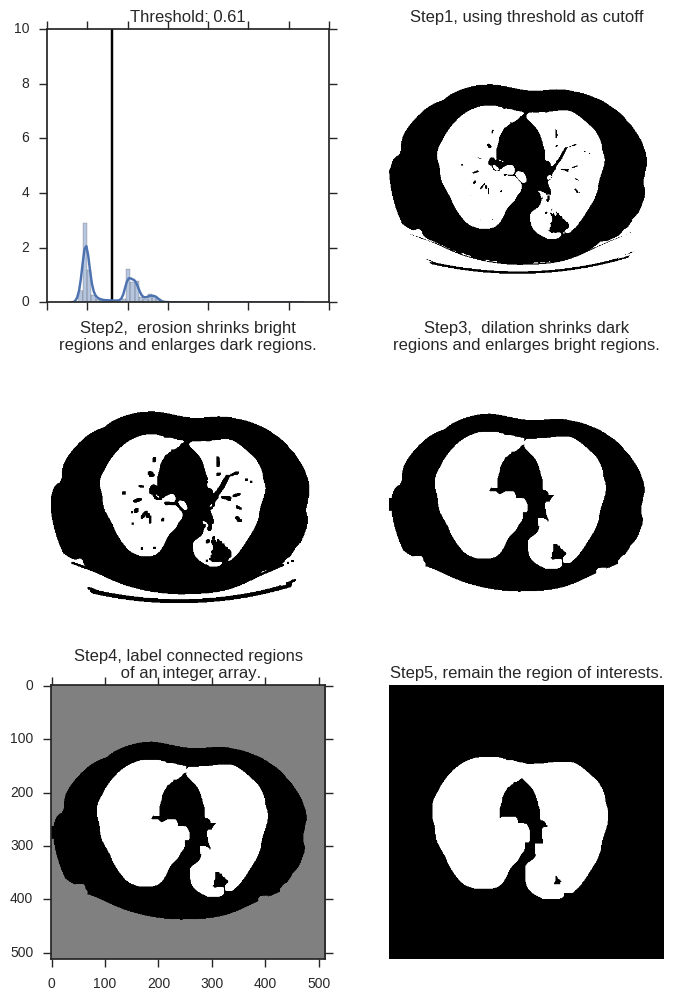

可见图中,除了中间亮度较低的肺部,还有亮度较高的脊柱、肋骨,以及肌肉、脂肪等组织。我们的一个思路,就是 留下暗的区域,去掉亮的区域。当然这里,亮度多高才算亮?这个我们可以对一张图中所有像素点的亮度做概率密度分布,然后用 Kmeans 算法,找出这个明暗分解的阈值(下文图中左上角):

然后使用 skimage 工具包。 skimage 是python一种传统图像处理的工具,我们这里,主要使用这个工具包,增强图像的轮廓,去除图像的细节,进而根据图像的轮廓信息,进行图像的分割,得到目标区域(Region of Interests, ROI)。

# 对一张图中所有像素点的亮度做概率密度分布, 用竖线标注阈值所在

# 展示阈值对图像切割的结果。小于阈值的点标注为1,白色。大于阈值的点标注为0,黑色。

# 增大黑色部分(非ROI)的区域,使之尽可能的连在一起

# 增大白色部分(ROI)的区域,尽可能的消除面积较小的黑色区域

# 上一张图中共有三片连续区域,即最外层的体外区域,内部的肺部区域,以及二者之间的身体轮廓区域。这里将其分别标出

# 提取regions 信息,这张图片的 region的 bbox位置分别在 [[0,0,512,512],[141, 86, 396, 404]],